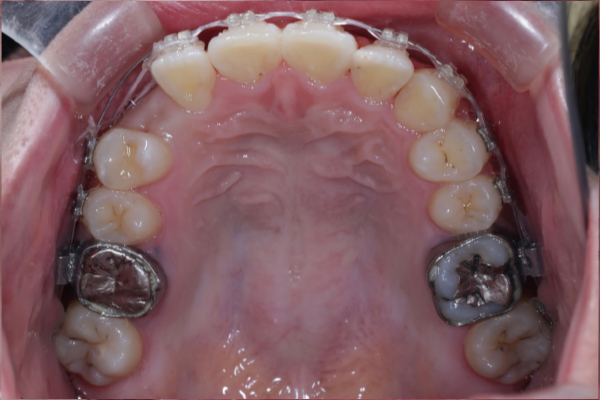

検査の結果、上顎犬歯が顎骨内に埋伏していることを確認しました。

自然萌出は困難と判断し、矯正治療による牽引で歯列内へ誘導する治療を計画しました。

残存していた乳犬歯を抜歯後、埋伏している上顎犬歯に対して外科的開窓を行い、矯正装置を用いた牽引を開始しました。

歯列に大きな叢生が認められなかったため、全体的な歯列バランスを維持しながら、スペース管理を行い慎重に犬歯の誘導を進めました。